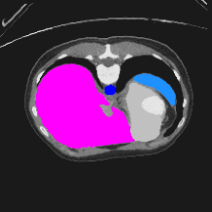

Transformers have made remarkable progress towards modeling long-range dependencies within the medical image analysis domain. However, current transformer-based models suffer from several disadvantages: (1) existing methods fail to capture the important features of the images due to the naive tokenization scheme; (2) the models suffer from information loss because they only consider single-scale feature representations; and (3) the segmentation label maps generated by the models are not accurate enough without considering rich semantic contexts and anatomical textures. In this work, we present CASTformer, a novel type of generative adversarial transformers, for 2D medical image segmentation. First, we take advantage of the pyramid structure to construct multi-scale representations and handle multi-scale variations. We then design a novel class-aware transformer module to better learn the discriminative regions of objects with semantic structures. Lastly, we utilize an adversarial training strategy that boosts segmentation accuracy and correspondingly allows a transformer-based discriminator to capture high-level semantically correlated contents and low-level anatomical features. Our experiments demonstrate that CASTformer dramatically outperforms previous state-of-the-art transformer-based approaches on three benchmarks, obtaining 2.54%-5.88% absolute improvements in Dice over previous models. Further qualitative experiments provide a more detailed picture of the model's inner workings, shed light on the challenges in improved transparency, and demonstrate that transfer learning can greatly improve performance and reduce the size of medical image datasets in training, making CASTformer a strong starting point for downstream medical image analysis tasks.